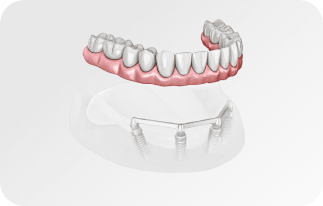

По уникальной методике

БЕЗ отёков и надрезов

Установка

за 1 день